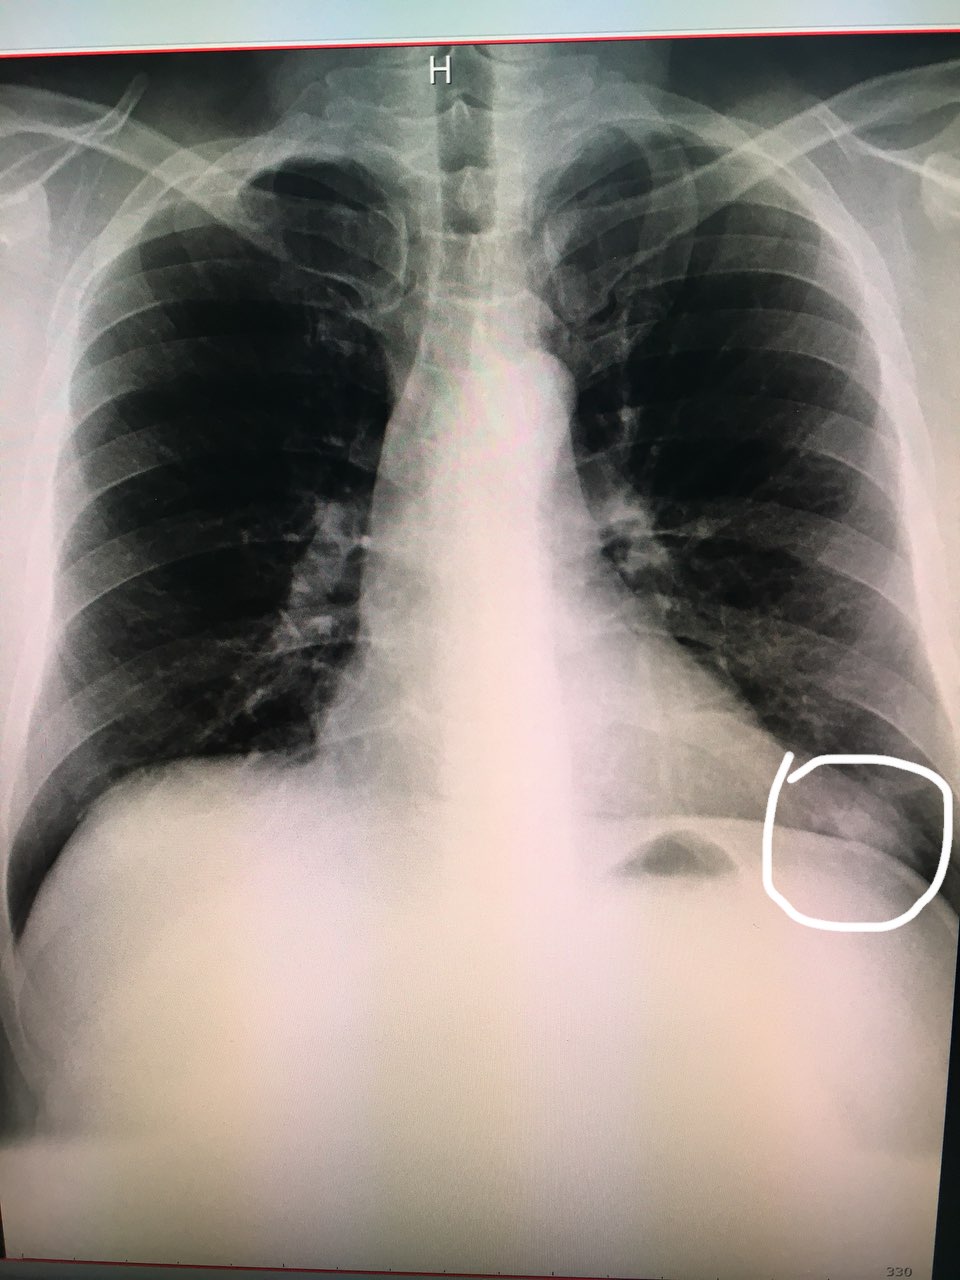

Коллеги, добрый день всем. Мужчина 45 лет, 2 недели назад по КТ поставили правостороннюю нижнедолевую пневмонию, прошёл курс лечения. Снимок сделали сегодня

Спиной не делали? Сосок?

Диск забрали к сожалению, а заключении КТ, сделанном неделю назад эта тень не описана

Спиной. Или доснять с меткой - сосок?

Спиной. Или доснять с меткой - сосок?

Что-то есть ☺️😏

Конечно диск бы увидеть

Унёс((( почему то кажется, что все таки сосок. Справа симметрично прохожая тень